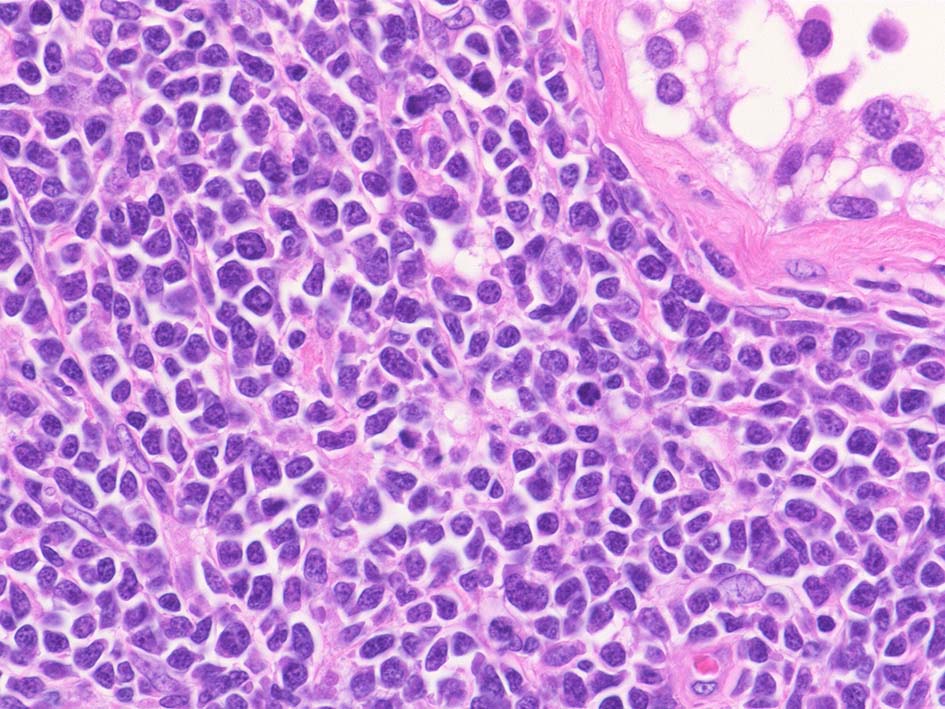

腫瘍内に壊死が認められる. 異型リンパ球の密な増殖により精細管は消失している.

腫瘍細胞はcentroblastic cells. mitosisやapoptosisが多い.